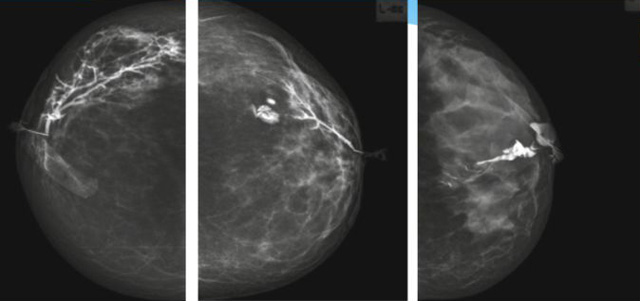

乳腺導(dǎo)管內(nèi)乳頭狀瘤分為以下兩個(gè),位于乳暈區(qū)大導(dǎo)管的中央型乳頭狀瘤,起源于末梢導(dǎo)管小葉單位的外周型乳頭狀瘤。外周型乳頭狀瘤常常沒(méi)有明顯的的臨床表現(xiàn),常因X線或乳腺超聲設(shè)備檢查發(fā)現(xiàn)。重點(diǎn)要關(guān)注的是中央型乳頭狀瘤,發(fā)生于任何年齡的女性,以40~50歲者居多。它表現(xiàn)為:單側(cè)乳頭溢液,特別是血性溢液少數(shù)病人可在乳暈區(qū)觸及腫塊。從病理學(xué)上面講表現(xiàn)為導(dǎo)管上皮和間質(zhì)增生形成有纖維脈管束的乳頭狀結(jié)構(gòu)。這是它一個(gè)病理學(xué)上的表現(xiàn)。它的超聲表現(xiàn)為:病變導(dǎo)管囊狀擴(kuò)張呈無(wú)回聲,內(nèi)可見乳頭狀低回聲或中等回聲。乳暈處的導(dǎo)管擴(kuò)張,管腔內(nèi)可見邊界清楚的,低回聲實(shí)性結(jié)節(jié)。外周型導(dǎo)管內(nèi)乳頭狀瘤可,表現(xiàn)擴(kuò)張為為低回聲的實(shí)性結(jié)節(jié),CDFI:部分腫瘤可顯示為軸心性的看到血流信號(hào)。乳腺增生癥:可見導(dǎo)管擴(kuò)張,內(nèi)無(wú)乳頭狀實(shí)性回聲,導(dǎo)管內(nèi)乳頭狀癌:囊內(nèi)乳頭狀癌病變較大,不規(guī)則,厚基底,血流豐富。以囊性為主的混合回聲,形態(tài)不規(guī)則,內(nèi)見實(shí)性低回聲實(shí)性低回聲可見少量血流,病理為囊內(nèi)乳頭狀癌。

乳腺超聲設(shè)備檢查的價(jià)值在哪里呢?它可以檢查發(fā)現(xiàn)乳暈周圍的各種病變,對(duì)于單側(cè)乳頭溢液、血性溢液的患者,超聲是首選的影像學(xué)檢查方法。注意:導(dǎo)管內(nèi)乳頭狀瘤可合并不典型增生或,導(dǎo)管內(nèi)乳頭狀癌,手術(shù)前懷疑時(shí)候,就應(yīng)該手術(shù)切除而不是用微創(chuàng)手術(shù)。